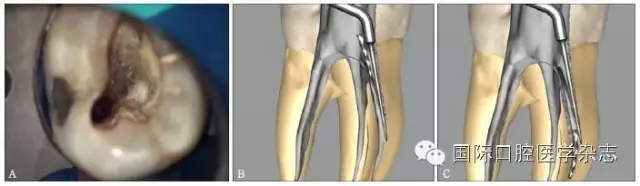

如果分離器械無法取出或取出的風(fēng)險(xiǎn)性較大,最佳處理方法就是繞過器械,將分離器械包裹于充填材料中(圖2)。不銹鋼和鎳鈦器械在根管內(nèi)不會(huì)腐蝕,因此相對(duì)無害??梢試L試用小的擴(kuò)孔鉆和銼繞過它。如果根管是橢圓形的,或者是不規(guī)則形的,分離的器械通常能夠被繞過。潤滑劑的使用有助于繞過分離器械。

3.2.3 繞過分離器械到達(dá)根尖的可能性評(píng)估 嘗試用小號(hào)(8號(hào)或10號(hào))預(yù)彎的手用銼沿著分離器械從旁邊通過。橢圓形的根管一般比較容易通過,而根管為圓形且分離器械阻斷了整個(gè)管腔時(shí),很難獲得通路。如果手用器械可以通過分離器械,則不斷用逐漸大號(hào)的手用銼來擴(kuò)大開口到達(dá)根尖,但注意使用時(shí)只能用輕柔的壓力。若不能通過分離器械,則不必強(qiáng)行制造通路,防止側(cè)穿發(fā)生。